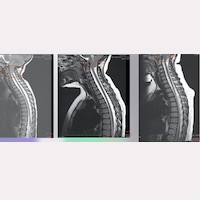

In our Institute’s caseload, this ascent is observed in some cases 1-2 years after surgery, while in others throughout the first 5-10 postoperative years (Fig. 1).